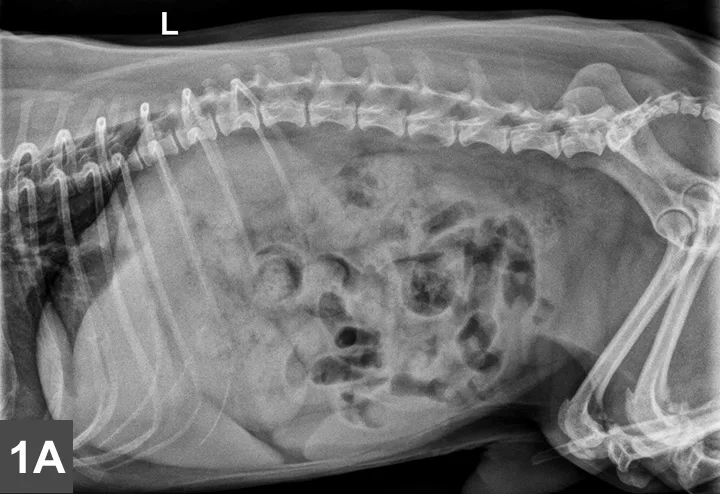

Left lateral (Figure 1A) and VD (Figure 1B) radiographs of the abdomen were obtained. Although thoracic radiographs were also taken, the findings were considered normal and, therefore, are not included here.

Figure 1A & B

Left lateral (Figure 1A) and VD (Figure 1B) views of the abdomen.